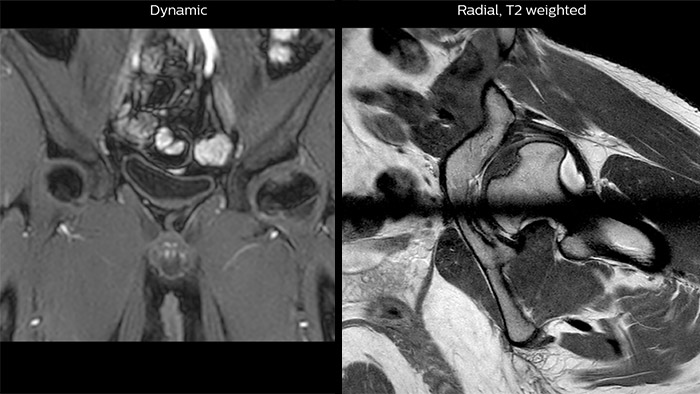

Crohn’s disease in the terminal ileum A large abscess is visible near the terminal ileum, in the middle of the coronal image.

Perthes disease in left hip The affected area on the upper circumference of the left hip shows contrast uptake in the dynamic scan. The radial scan nicely depicts the hip area, despite the dark shape in the center that is inherent to the radial way of scanning.